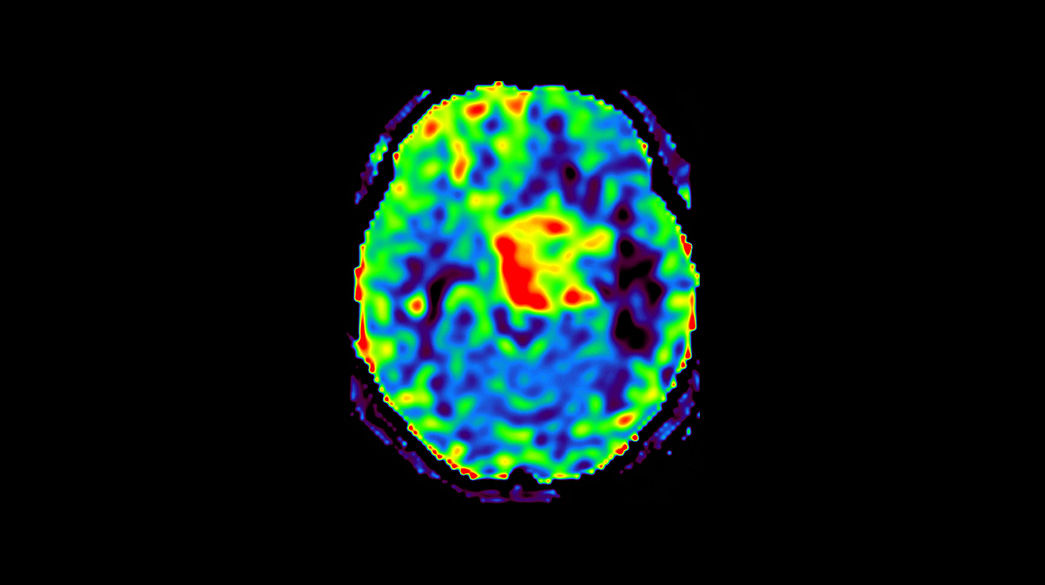

3D-Arterial-Spin-Labeling3DSpin1040-x-585

Read case study ico-caret-right